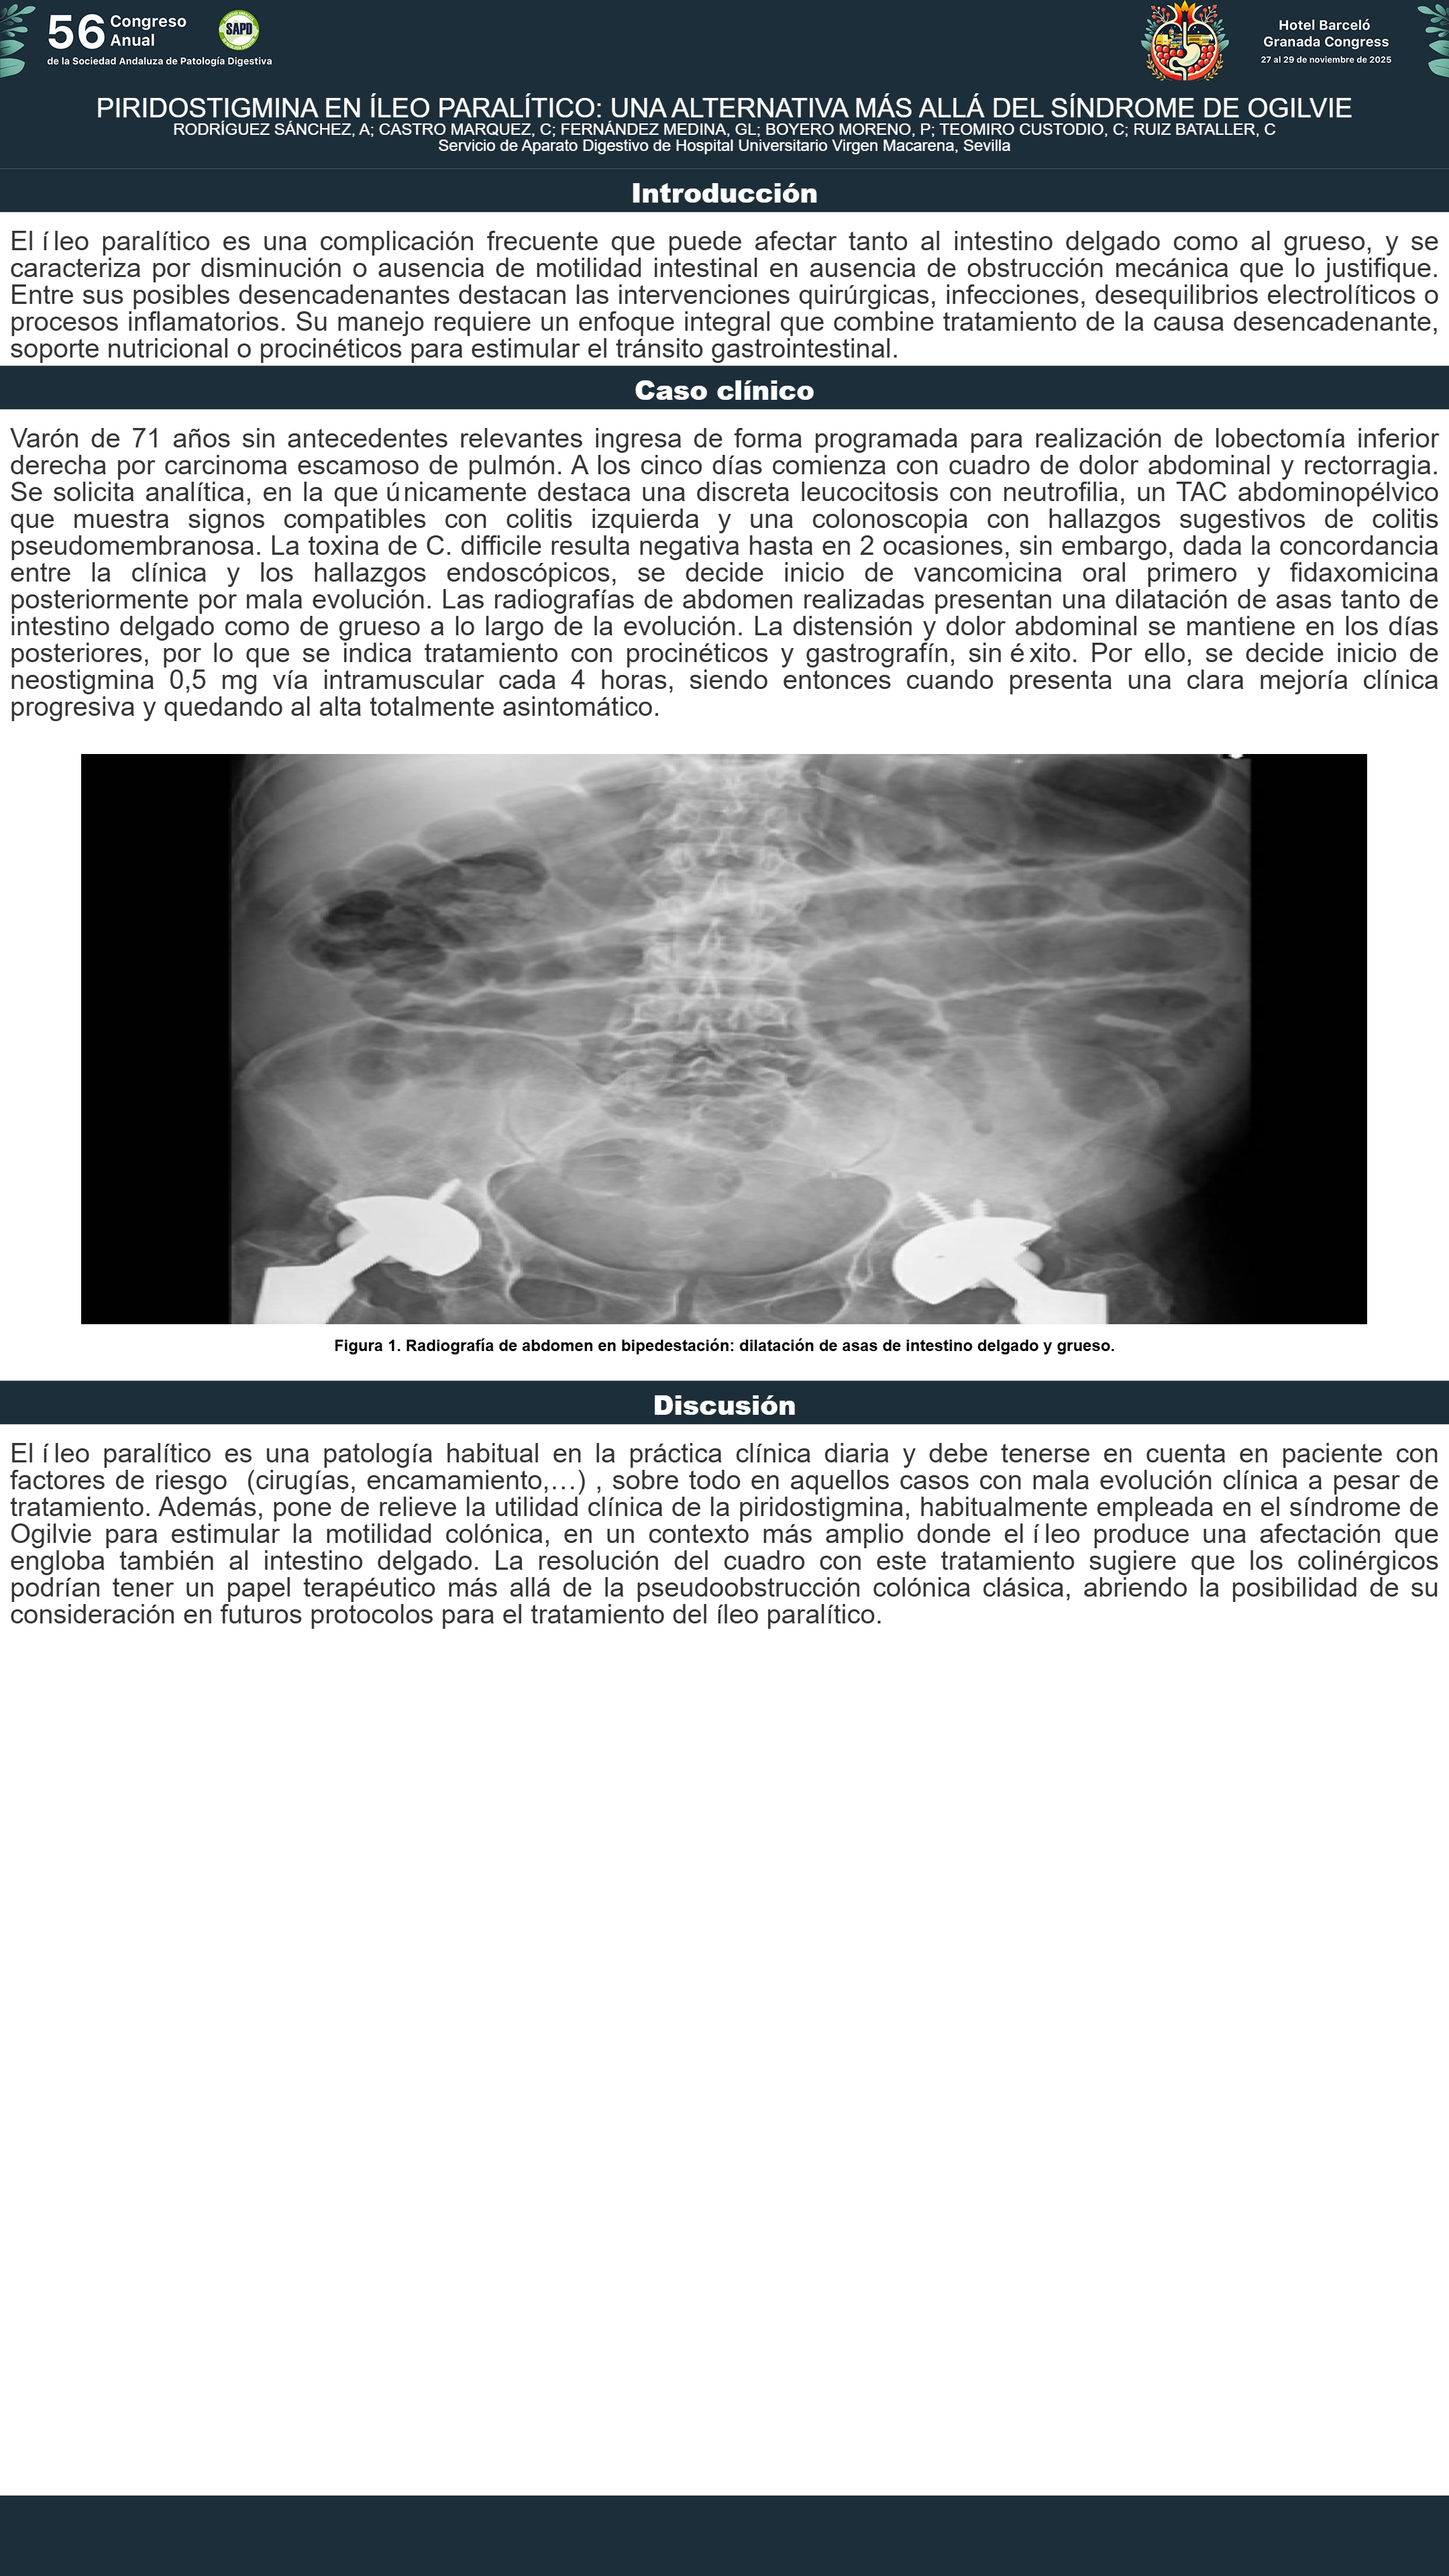

[CP-121] PIRIDOSTIGMINA EN ÍLEO PARALÍTICO: UNA ALTERNATIVA MÁS ALLÁ DEL SÍNDROME DE OGILVIE